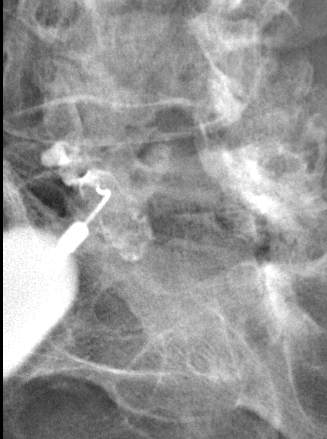

Radiographie de l'épaule. L'épaule a 2 articulations : l'articulation acromio-claviculaire (flèche pleine) et l'articulation omo-humérale (flèche creuse).

Infiltration de l'articulation omo-humérale (épaule).

Après ponction directe de l'articulation, il est injecté du produit de contraste afin de s'assurer de la position intra-articulaire de l'aiguille avant d'injecter l'anti-inflammatoire.